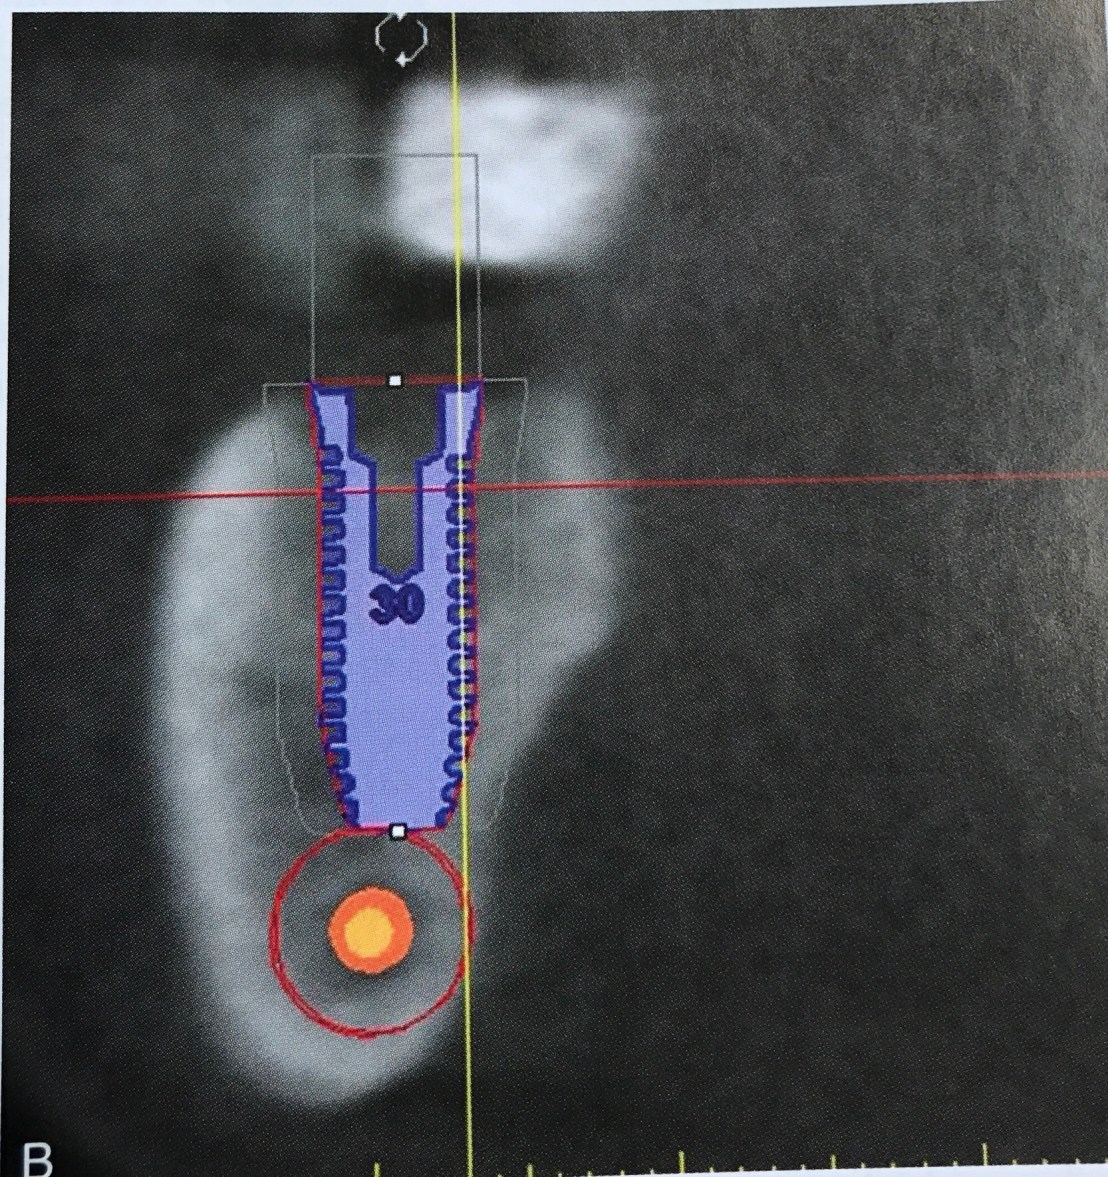

แสดงตำแหน่ง Ideal คือ ปลาย Implant ห่างจาก nerve มากกว่า 2 มม.

Software แสดง Safety zone

ทำไมต้องเป็น 2 มม.?

คำตอบคือ injury ชนิด Neurapraxia สามารถเกิดขึ้นได้จาก Compression necrosis ระยะที่ใกล้ไม่ถึง 2 มม. แม้ไม่ invade nerve โดยตรง แต่แรงจากการกดจะส่งผ่านกลไก Compression-related injury ได้